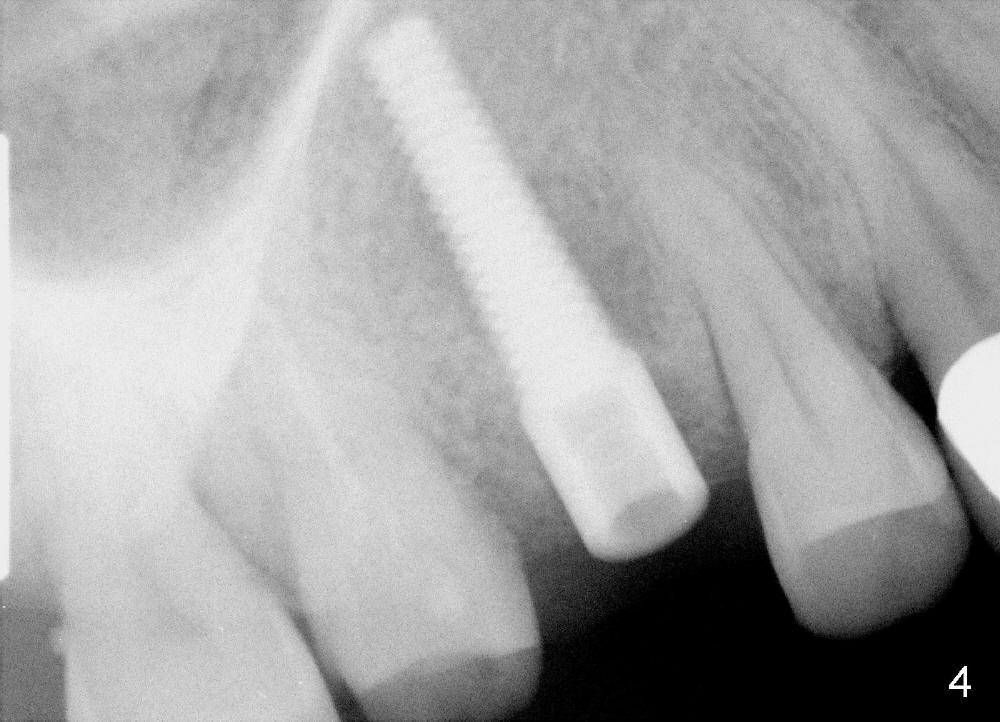

When the tooth #4 is extracted, the apical socket is found to be large with granulation tissue, which is consistent with large periapical radiolucency (Fig.2 arrowheads). The depth of the socket is 17 mm, measured from the gingival margin. The mesiodistal and buccolingual dimensions of the root are 4 and 7 mm, respectively. A tissue-level tapered implant as wide and as long as possible, 4.5x20 mm, is to be placed (Fig.3 (tap drill), 4). The insertion torque is between 35 and 40 Ncm.